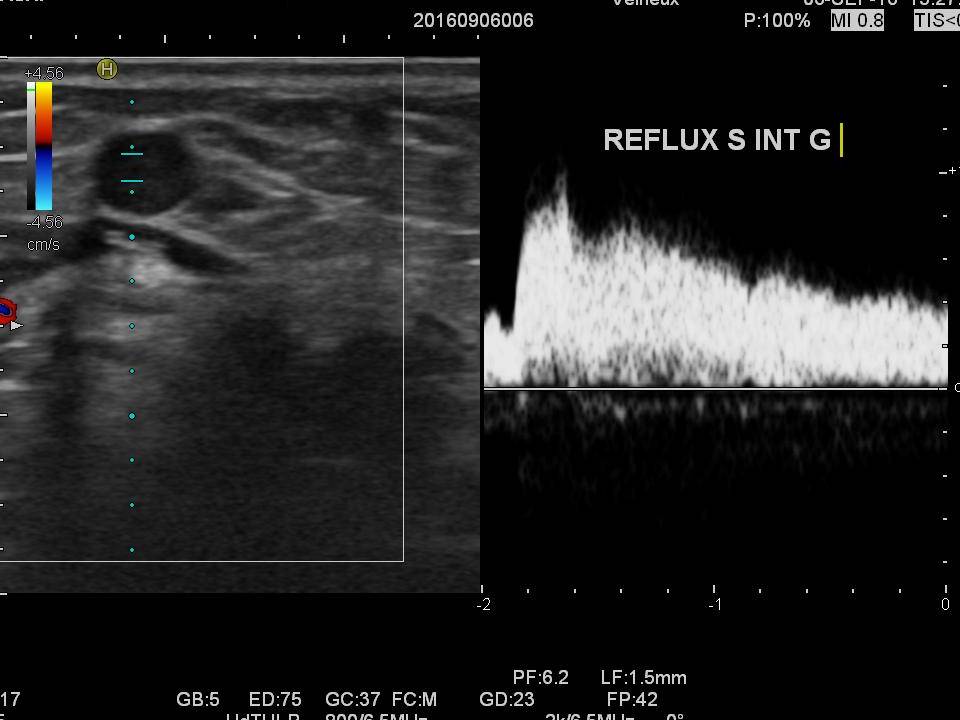

Echo-doppler veineux des membres inferieurs

explorer le réseau veineux superficiel et profond des membres inférieurs (photo).